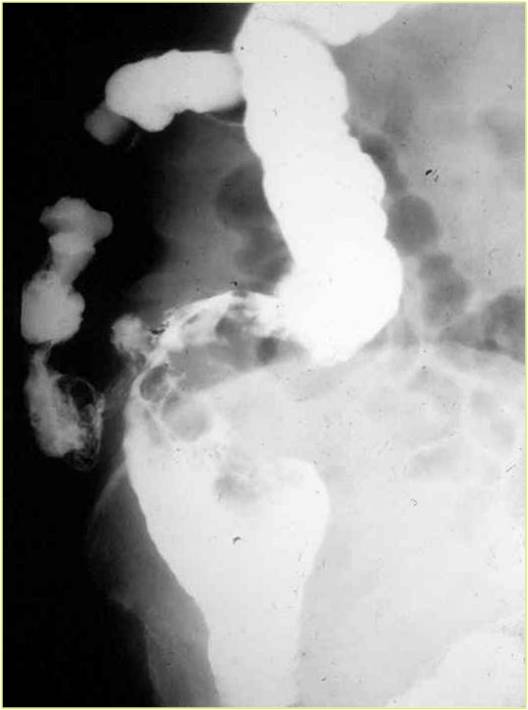

Image

Fig.3.: Pseudo-diverticulosis

Radiographic findings: rosary-bead like outpouchings of the esophagus. Static peristaltic waves are seen. These are ineffective in passing forward the esophageal contents.